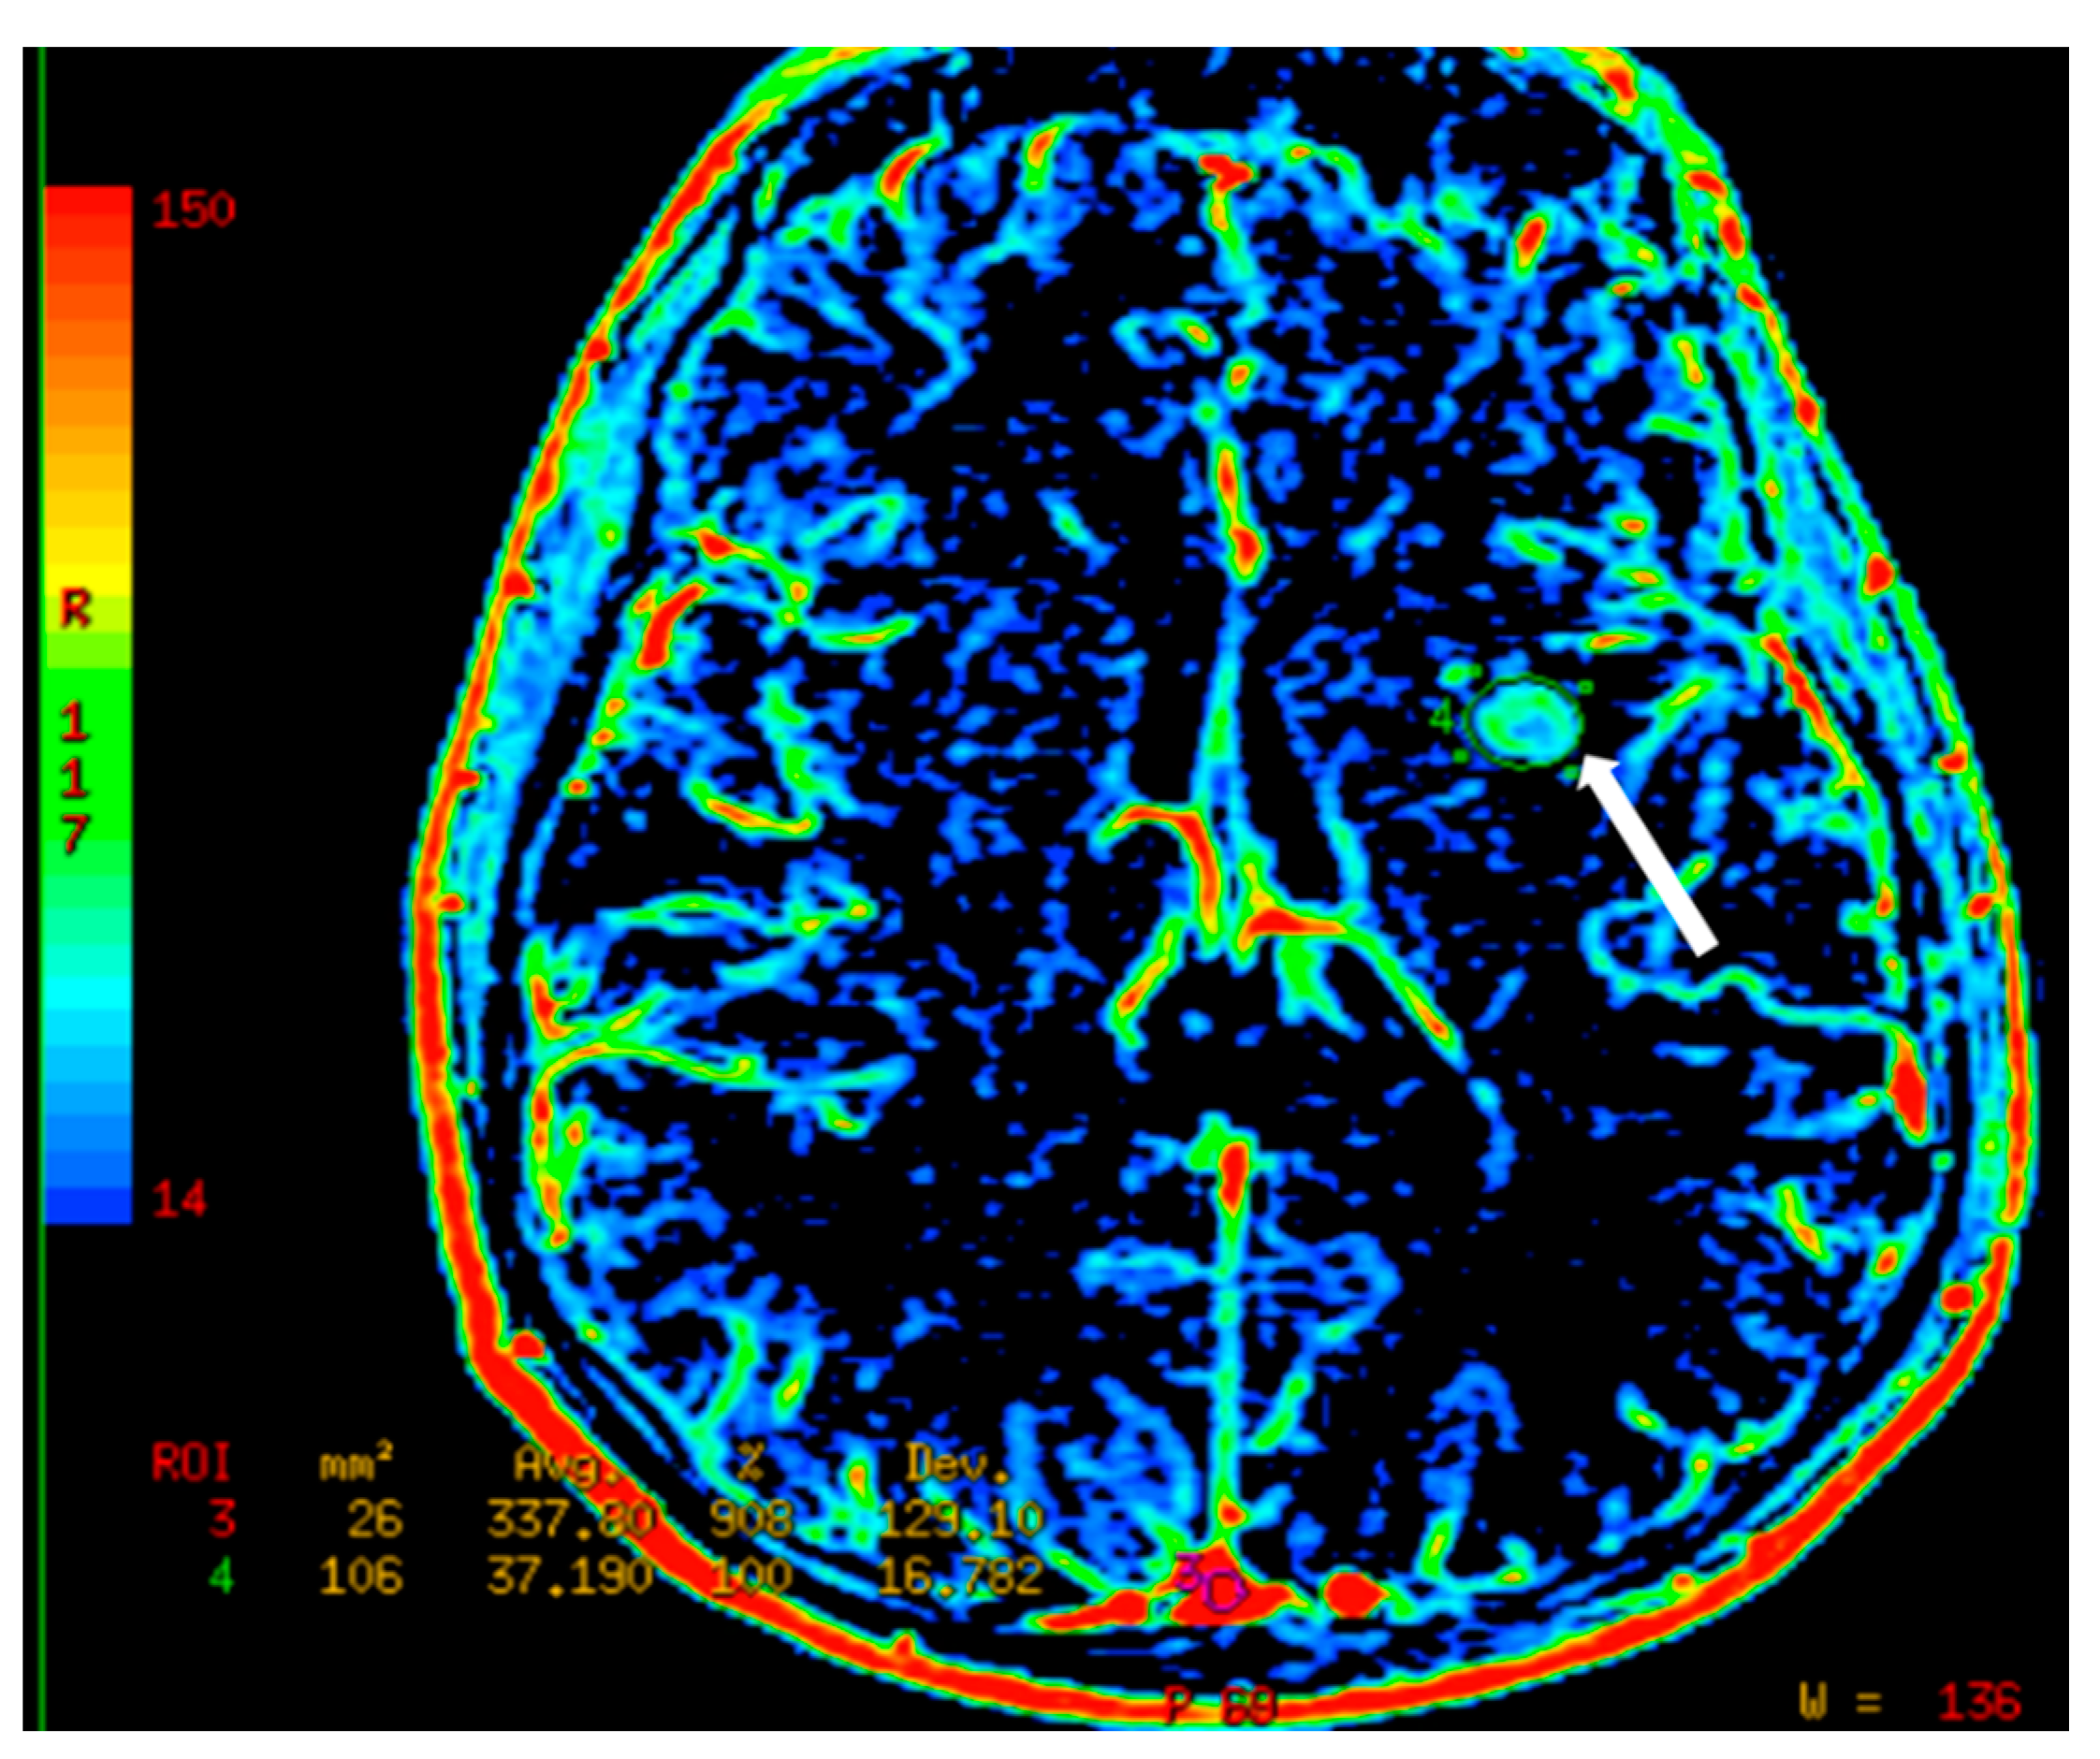

8. CT Imaging of Angiogenesis

8.1. Multi-Slice Computed Tomography (MSCT) Perfusion Imaging Technique

8.2. Clinical Applications of CT Perfusion

- D’Assignies, G.; Couvelard, A.; Bahrami, S.; Vullierme, M.; Hammel, P.; Hentic, O.; Sauvanet, A.; Bedossa, P.; Ruszniewski, P.; Vilgrain, V. Pancreatic endocrine tumors: Tumor blood flow assessed with perfusion CT reflects angiogenesis and correlates with prognostic factors. Radiology 2009, 250, 407–416. [Google Scholar] [CrossRef]

- Xu, N.; Lei, Z.; Li, X.L.; Zhang, J.; Li, C.; Feng, G.Q.; Li, D.N.; Liu, J.Y.; Wei, Q.; Bian, T.T.; et al. Clinical study of tumor angiogenesis and perfusion imaging using multi-slice spiral computed tomography for breast cancer. Asian Pac. J. Cancer Prev. 2013, 14, 429–433. [Google Scholar] [CrossRef] [PubMed]

- Sun, C.H.; Feng, S.; Xiao, P.; Peng, Z.P.; Pui, M.H.; Li, X.H.; Li, Z.P.; Meng, Q.F. Quantitative assessment of perirectal tumor infiltration with dynamic contrast-enhanced multi-detector row CT in rectal cancer. Eur. J. Radiol. 2011, 80, 279–283. [Google Scholar] [CrossRef]

- Mazzei, F.G.; Mazzei, M.A.; Cioffi Squitieri, N.; Pozzessere, C.; Righi, L.; Cirigliano, A.; Guerrini, S.; D’Elia, D.; Ambrosio, M.R.; Barone, A.; et al. CT perfusion in the characterisation of renal lesions: An added value to multiphasic CT. BioMed Res. Int. 2014, 2014, 135013. [Google Scholar] [CrossRef]

- Trojanowska, A.; Trojanowski, P.; Bisdas, S.; Staśkiewicz, G.; Drop, A.; Klatka, J.; Bobek-Billewicz, B. Squamous cell cancer of hypopharynx and larynx—Evaluation of metastatic nodal disease based on computed tomography perfusion studies. Eur. J. Radiol. 2012, 81, 1034–1039. [Google Scholar] [CrossRef] [PubMed]

- Liu, Y.; Bellomi, M.; Gatti, G.; Ping, X. Accuracy of computed tomography perfusion in assessing metastatic involvement of enlarged axillary lymph nodes in patients with breast cancer. Breast Cancer Res. 2007, 9, R40. [Google Scholar] [CrossRef]